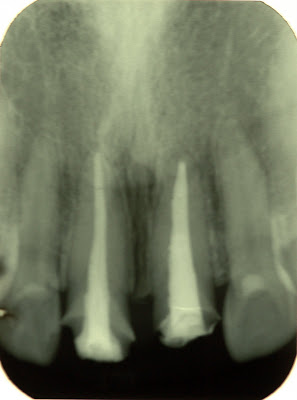

(轉貼圖:抽調神經後的牙齒,在X光片上顯現,換呈現出來是白的.) 我想,我從小到大,看過做多次的醫生,應該是牙醫了吧。小時候是因為蛀牙,長大是因為例行檢查。但為什麼我總是有一堆亂七八糟的問題,醫生一個換過一個,每次照完X光,給我看的片子,都讓我驚訝到不行。 護士:不好意思,你的神經已經被抽掉了,最好是做假牙比較好。 我:神經被抽掉!!什麼時候的事情,看了片子後,確認真的沒了。 (所以我才常常少根經嗎) 我:如果沒有神經以後會怎樣? 護士:沒有神經的牙齒,牙齒就跟死掉了一樣,因為沒有神經供給營養,牙齒會變薄、變脆弱、而且會隨著時間越來越黯淡。然後馬上跟你講價錢,貴金屬(台灣、進口),全瓷&*%&$︿%#$ 我:所以沒有神經的牙齒一定要換假牙就對了。 護士:是啊!(再跟你扯一堆)*︿&%&︿$ 我:不好意思喔~我要跟家人討論一下,下次再你答覆。 後來下次去,決定要做了,這位醫生更厲害,由於我是做醫學美容的,我建議你,要好看的話,一整排六顆都做。下排牙齒再做一些陶瓷貼片,保證你整個人變漂亮。 心中OS:奇怪?!我到底是來看牙醫,還是來整容啊?!而且我牙齒好好的,為什麼要做六顆假的牙?! 當然,原本我決定要做的牙齒,被醫生這樣一搞,我決定不做了。 詢問一些懂醫療方面的朋友,再找一些書跟網路搜尋。 找到這篇文章,是我最最讚同的做法。 不是因為我不想換,就找文章來驗證自己。 而是因為,如果抽了神經的牙齒,就沒有他的價值。那為什麼我不知道自己已經被抽神經的狀況下,那顆牙齒還可以一直好好的存在。 我要的不是變漂亮,需要的是真實的身體,為什麼現在為了美,把全身上下的真實都換成人工的,就算打造出一個完美的容貌,那又如何?!(此段文句,無意冒犯真的需要矯正的朋友。) 抽除神經的活死牙 仍有重要使命 相信有許多人都曾經聽過抽神經這三個字,就字面上看來它相當令人害怕 要將你的神經抽出,這是一件多麼駭人聽聞的事情呀,其實它不如字面上所表現的意思它只是將牙齒中壞掉的東西清除乾淨,且治療過程中也不如想像中可怕 況且這項治療是將真牙保存下來的最好方法抽神經是牙科根管治療中的一個步驟,我們每個牙齒中間都有一個空間即牙髓腔,這樣一個空腔的中間包含了神經 血管,淋巴及一些其他組織的分布而根管治療就是針對此一空腔所做的治療正確的根管治療包含: 1.去除牙髓組織 2.根管沖洗及根管擴大 3.根管填充 4.恢復牙齒的型態及功能 需要根管治療的牙齒通常是牙髓已經發生病變、發炎、引起疼痛導致壞死, 甚至最後形成牙根尖周圍齒槽骨病變吸收,經過根管治療後,可將牙齒保留下來而不需拔除,但也因牙髓組織已清除,所以齒質會漸漸脫水及礦物質化使牙齒變脆而失去彈性且需根管治療的牙齒通常蛀蝕得相當厲害,若不適當保護牙齒,極易斷裂而前功盡棄因此在根管治療後有必要裝上牙柱,以加強牙齒結構,並套上牙冠以保護牙齒,恢復美觀發音及咬合功能。 牙齒中牙髓的存在空間十分細小,所以根管治療的過程是非常精細及困難的 醫師運用特殊設計的小號器械,將發炎、壞死的部部清除乾淨,適度擴大牙髓腔,並使用適當。材料將其細密填充,以取代原有牙髓所佔有的空間,在治療中包含了精確的測量及不妡的擴大,沖洗的過程,需要多次的治療時間才能完成,所以醫師提醒民眾對於療程一拖再拖的病患,除了必須忍受牙齒疼痛的發作外,還可能面臨牙髓發炎擴散導致周遭齒槽骨發炎的危險,嚴重時可能會導致蜂窩性紅織炎 及臉頰腫脹其至細菌就可以順著血液流到全身,引發全身菌血症而危及性命。 雖說根管治療過後的牙齒,已經沒有神經,但血管可維持牙齒的活性可以說是一個活死牙,但是它的存在可以保持天然牙齒排列的完整性,預防鄰接牙齒的移位,蛀牙、牙周病的發生,也防止拔牙後的支抾骨質喪失過多,影響臉形的外觀及假牙穩定性更由於牙齒的保持可解決若干假牙製作上的困難,所以根管治療除了將牙髓清乾淨之外更有將牙齒保留下來的重要使命。 一般在進行根管治療時,若是牙髓炎的牙齒都會在局部麻醉中進行,只要上了麻藥即能在舒適無痛的狀況下接受治療,有些人在治療後仍會有疼痛的現象 此乃牙齒周圍組織有暫時性的炎性反應,簡單的止痛藥即能控制,但若有劇烈的疼痛或腫脹,吃止痛藥也無法改善時,就應該再找醫師做詳細的診療。 轉貼自:http://bbs.nsysu.edu.tw/txtVersion/boards/medicine/M.1091069895.A.html ----------------------------------------------------------- |